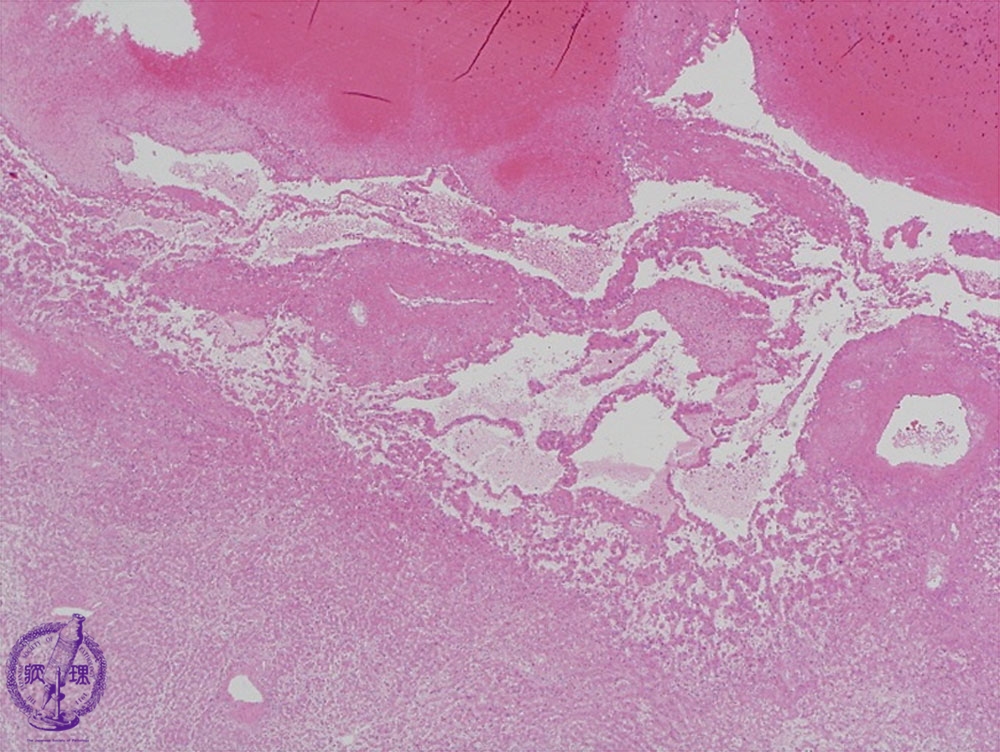

- ★(14)Angiosarcoma of the liver

Microscopic image (HE stain, low power): The boundary (yellow dashed line) between tumor and non-neoplastic liver is unclear.